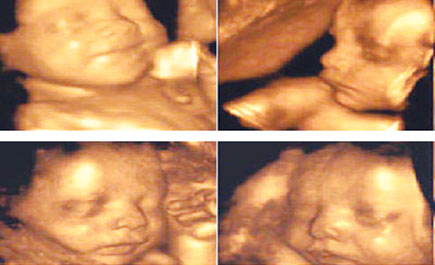

اعرفي الخطأ والصواب.. في حملك

سيدتي الحامل.. هناك بعض المفاهيم الخاطئة ينبغي عليك معرفتها وتصحيحها، نذكر لك أشهرها وأهمها: الخطأ: يعتقد البعض أن كبر بطن المرأة الحامل دليل على كبر حجم الجنين. الصواب: هذا غير صحيح... فهناك عدة تغيرات تحدث في منطقة البطن والحوض ويعزا ذلك إلى حدوث ارتخاء في منطقة حزام البطن...>>>...